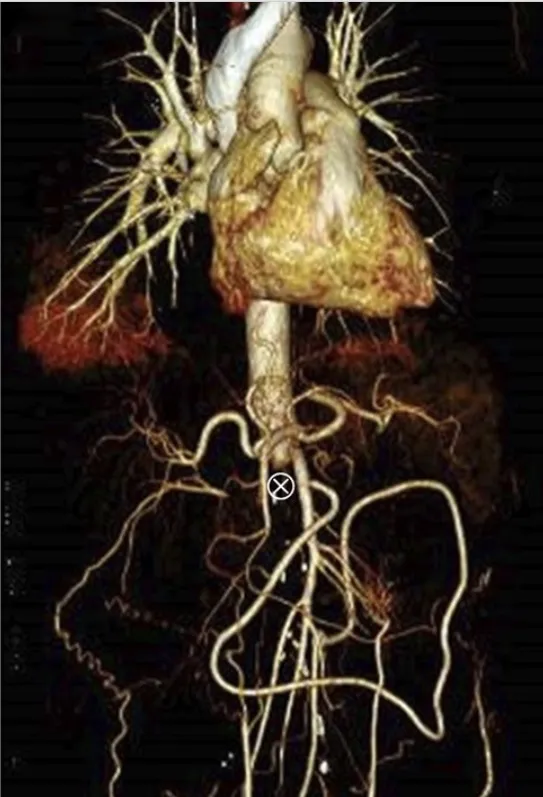

Dor lombar súbita e hipotensão em um paciente que o nefrologista é chamado para auxilar na investigação, quais pontos importantes do diagnóstico não podemos esquecer?